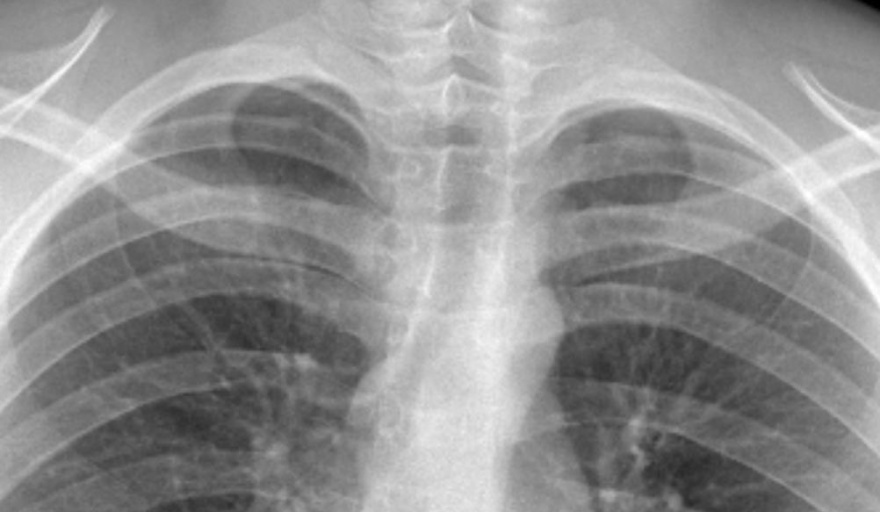

El servicio de Cirugía General del Hospital Interzonal San Juan Bautista realizó una intervención quirúrgica compleja e inédita para extraer una aguja de coser alojada en el pulmón de un paciente de 16 años, oriundo de Tinogasta, quien ingresó por guardia tras sufrir un accidente doméstico. El hecho ocurrió cuando el joven se apoyó sobre una caja que contenía un objeto metálico, que le provocó un trauma penetrante de tórax.

Tras una primera atención en su lugar de origen, fue derivado al hospital, donde se confirmó la presencia del cuerpo extraño en el pulmón. El equipo de Emergencias, ni bien ingresado, realizó el drenaje torácico mediante la colocación de un tubo para la evacuación de aire, secreciones y sangre; como el pulmón no lograba expandirse debido a la presencia del objeto, se procedió a la planificación de la resolución quirúrgica.

Por su parte, el equipo de Anestesiología, con uso de fibrobroncoscopio realizó una intubación selectiva, técnica que permite ventilar un solo pulmón mientras el otro se mantiene sin funcionamiento, lo que posibilita intervenir directamente sobre el pulmón afectado, mejorando la visibilidad y reduciendo riesgos durante la extracción.

En este sentido, el Dr. Lestussi explicó: “Se trató de un trauma penetrante de tórax con un objeto metálico que resultó ser una aguja de coser, clavada en el pulmón. Era un caso que no podía derivarse por el riesgo que implicaba el traslado, por lo que la resolución debía hacerse en nuestro hospital, y con mucha satisfacción podemos decir que lo realizamos profesionales del hospital”.

Además, destacó la labor del Servicio de Anestesiología, “La intubación selectiva fue clave, ya que permitió trabajar sobre el pulmón comprometido en condiciones seguras, mientras el otro continuaba garantizando la oxigenación del paciente”.